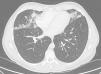

Posteroanterior and lateral chest radiographs and thoracic computed tomography (CT) showed the presence of irregular nodules (acinar) and alveolar infiltrates in the middle lobe, lingula and lower lobes, with perilymphatic and subpleural distribution (Fig. 1). Pulmonary function tests were normal, with FVC 4830ml (97%), FEV1 3870ml (93%), FEV1/FVC 80%, DLCO 94%, KCO 94% and VA 97%. We ordered a thorough complete blood analysis and bronchoscopy with transbronchial biopsy by cryocatheter.

The most common radiologic findings are bilateral nodular opacities, generally smaller than 3mm, although cases with opacities larger than 12mm have been described, with centrilobular or peribronchiolar distribution. Bilateral patchy areas of ground glass opacities can be seen with non-segmental distribution.8